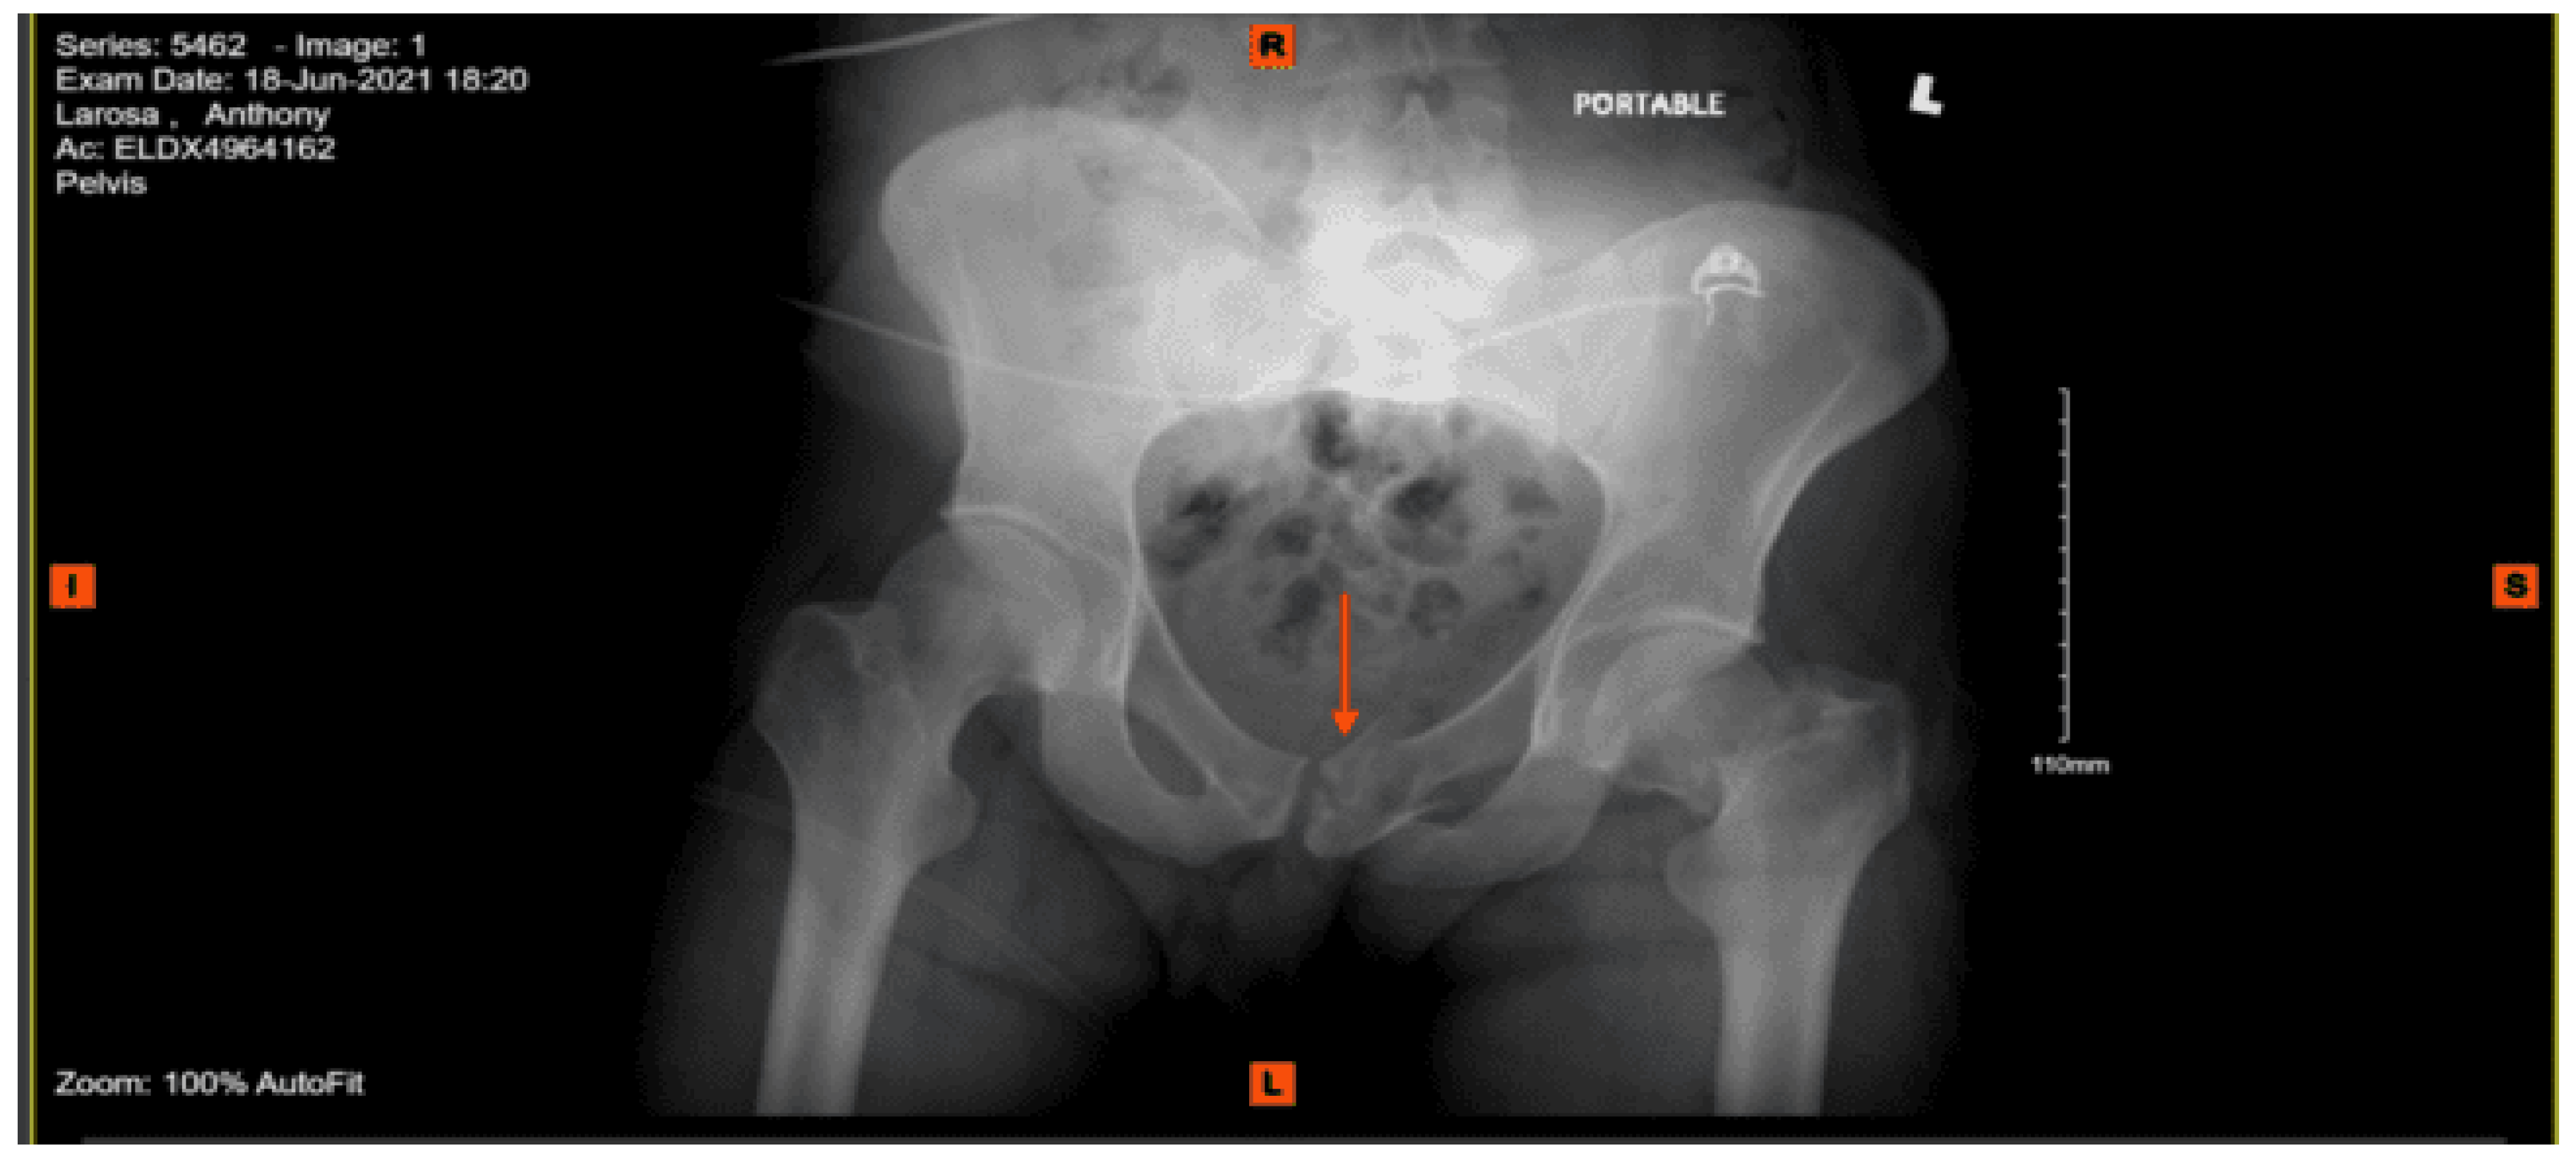

Portable pelvis X-ray: Degenerative changes about both hips. Probable subcapital fracture of the right hip. Marked concentric narrowing of the joint space of the right hip. Osteopenia.

CT abdomen pelvis with contrast: Grossly intact abdominal and pelvic viscera with acute fracture of the left superior pubic ramus near the symphysis and the bilateral inferior pubic rami.

CT lumbar spine without contrast: Diffuse osteopenia of the lumbar spine with suggestion of a fracture involving the anterior aspect of the vertebral body of L5 in its superior portion and acute fracture of the anterior aspect involving the lateral mass of S1